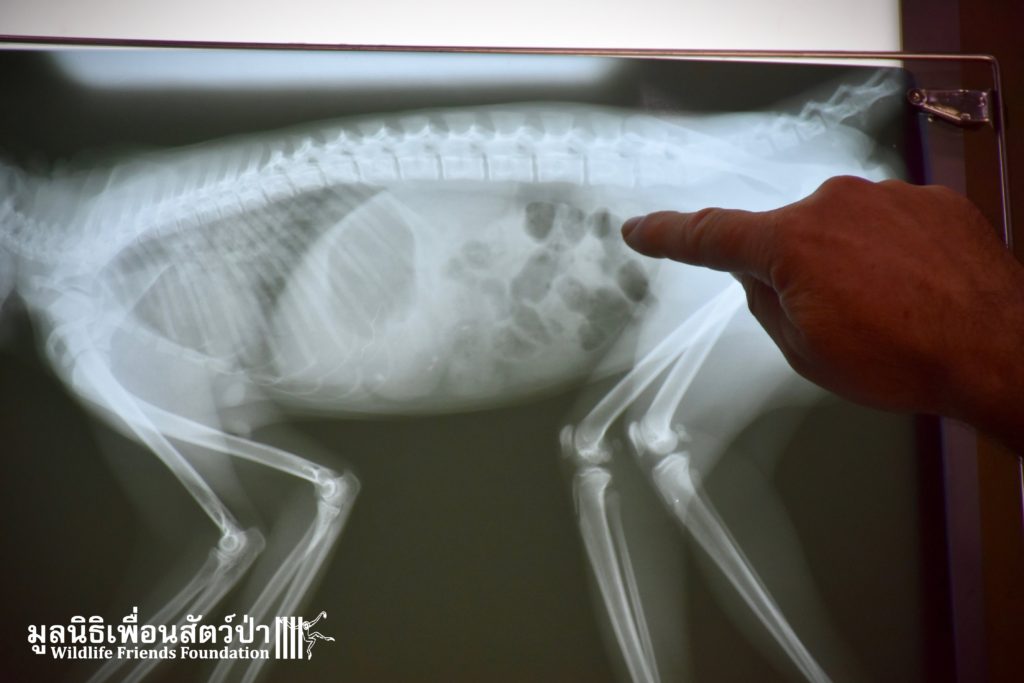

This temple is inhabited by a large population of macaques. Since the rescue team arrived they were observing the situation, many of the monkeys took an interest in what the team were doing, they needed to act fast to avoid any conflict with the concerned monkeys. Once the monkey had been transported to the rescue vehicle, the decision has been made to take her to a clinic to take on x-ray to access her further. The X-ray didn’t reveal any major broken limbs, just a small fracture on a toe but because had big secreting fluid from the anus, the vet decided to ask for further examinations.

She was not doing well and her body was showing that she had some internal problem. With the ultrasound scan, the trauma has been identified: gas and blood clot in her lungs and bladder. She was too unstable. No possible surgery. With only 50% chance of making it she was taken to the WFFT Wildlife Hospital for further treatment. Sadly, a few hours after arriving she passed away. Her injuries were too severe and she was inoperable. Internal bleeding took her away. Rest in peace little one.